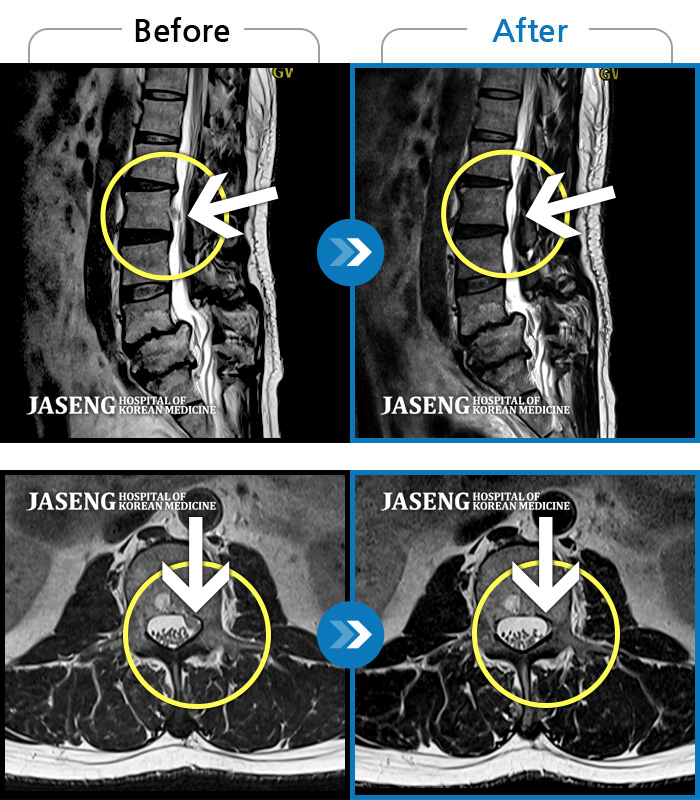

- MRI ġ

MRI ġ

1,240 MRI ũ ʸ Ȯϼ.